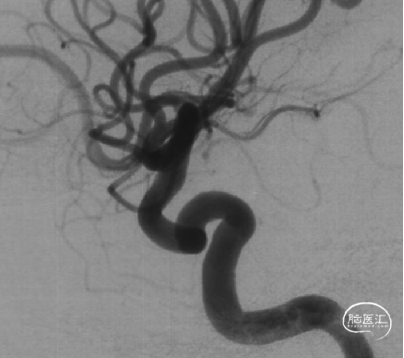

现病史:患者因头痛17天,外院行头颅CTA提示:左侧颈内动脉交通段动脉瘤,动脉瘤大小约5.3×5.4mm,形态不规则,左侧大脑前动脉A1段瘤样凸起。

可见一小泡自动脉瘤瘤体上发出

瘤体最大径6.92mm

远端血管直径:3.28mm

近端血管直径:3.98mm

同侧A1可见一小瘤突起